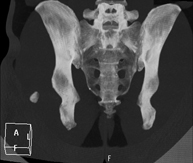

- Pelvic bone CT

Radiological examination based on an X-ray system and detectors that rotate around the patient, reconstructing the images by computer (multidetector computed tomography - MDCT) to study the bones, muscles and joints of the pelvis.

- Hip CT

Radiological examination based on an X-ray system and detectors that rotate around the patient, reconstructing the images by computer (multidetector computed tomography - MDCT) to study the bones, muscles and joints of the hips.

- Sacroiliac CT

Radiological examination based on an X-ray system and detectors that rotate around the patient, reconstructing the images by computer (multidetector computed tomography - MDCT) to study the sacroiliac joints and rule out inflammatory, traumatic or degenerative diseases.